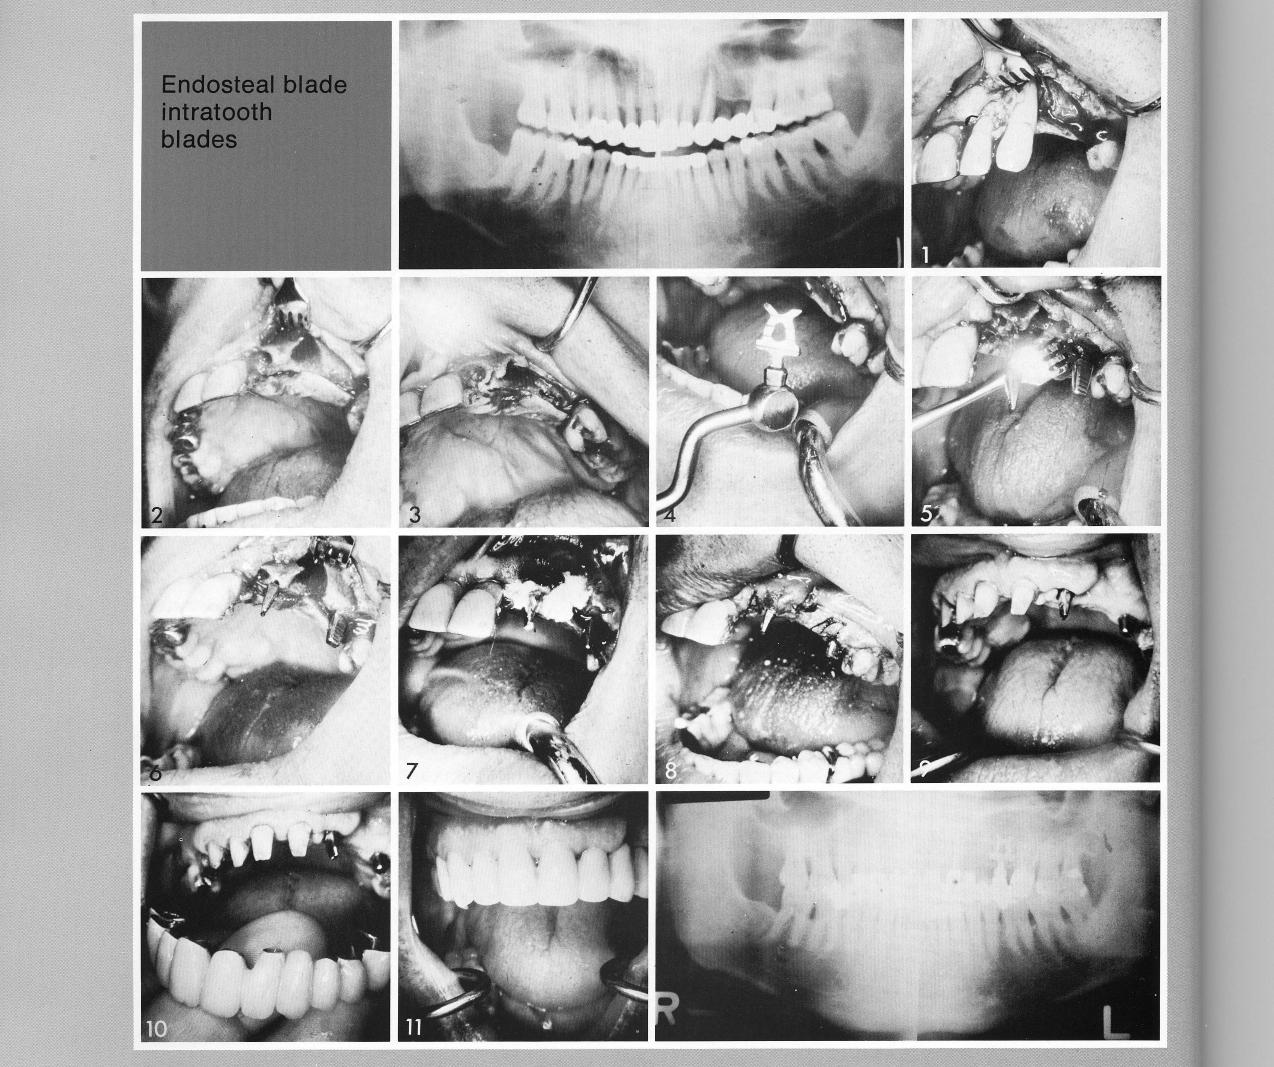

Intra-tooth blade support

Often working in a short span between two teeth produces more problems than does working in a totally edentulous arch. In this patient, a cuspid almost totally exposed on its labial surface (2) left a large socket, while the loose lateral incisor left a small socket (2,3). A trimmed bladevent (4) was seated behind the cuspid socket. A single-tooth bladevent was seated across the arch bucco-palatally (5,6) in the small space between the open sockets. Sterile plaster of Paris (7) was used in the socket to encourage healing. After the implant sites healed, the teeth were prepared (9) for inclusion in a full arch prosthesis.

1 A trimmed maxillary bladevent implant seated

2 A single maxillary tooth bladevent implant seated across the arch